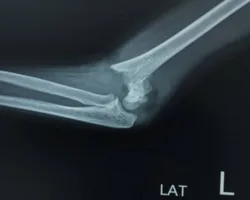

Elbow Fractures & Dislocations

Injuries caused by trauma to the elbow, resulting in broken bones or dislocated joints, often requiring surgical intervention for proper alignment and healing.